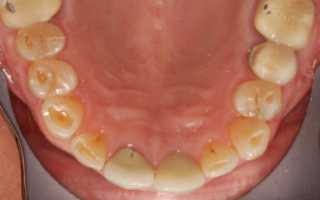

Начальная стадия кариеса с зубным налетом, которая поддается лечению в домашних условиях.